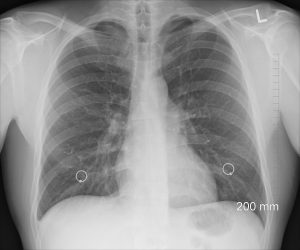

Polmonite

PolmoniteLa polmonite è dovuta all’infiammazione degli alveoli polomnari ed è una patologia piuttosto conosciuta ma spesso sottovalutata. Quando infiammati, gli alveoli si riempiono di liquido creando problemi di respirazione e riducendo la capacità polmonare del paziente. Si tratta di una malattia seria, che non deve mai essere tracurata e deve anzi essere trattata con una certa tempestività perchè potrebbe peggiorare e determinare altri problemi a carico dell’apparato respiratorio…continua a leggere